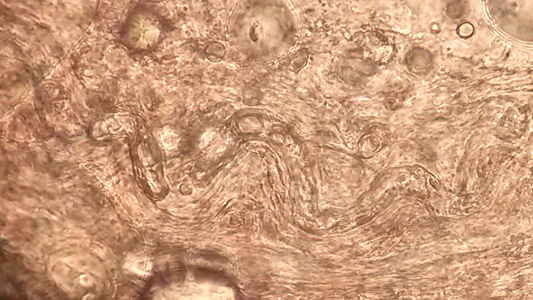

DPDx is an educational resource designed for health professionals and laboratory scientists. For an overview including prevention, control, and treatment visit www.cdc.gov/parasites/.